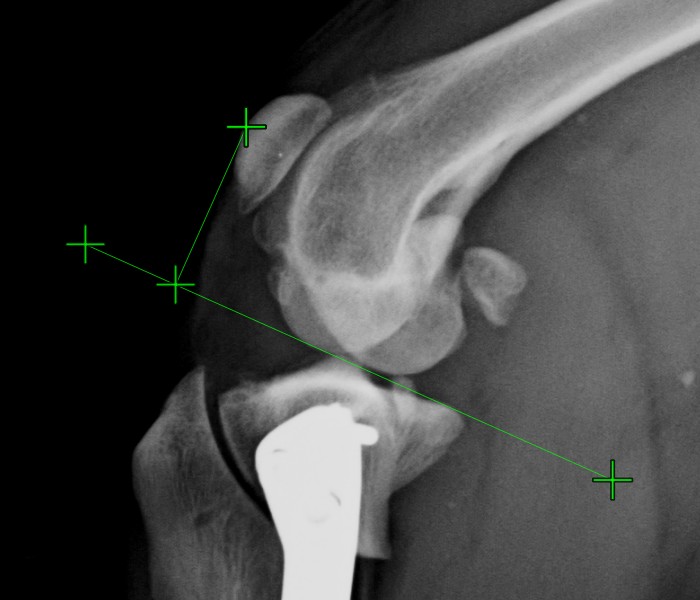

The measurements and their description and subtitles can be hidden by using the Hide/Show Measurements and Subtitles button in the viewer toolbar. Depending on the active state of the measurements, the button is accordingly updated.

The button always shows the current active state of the measurements.

Change this setting individually for each measurement by using the measurement list.

All of the measurements are still visible in the viewer area, however their description and subtitles are hidden.

Additionally, the visibility of the measurements in the viewer area can be toggled by using the Menu -> Show measurements option from the Viewer menu.